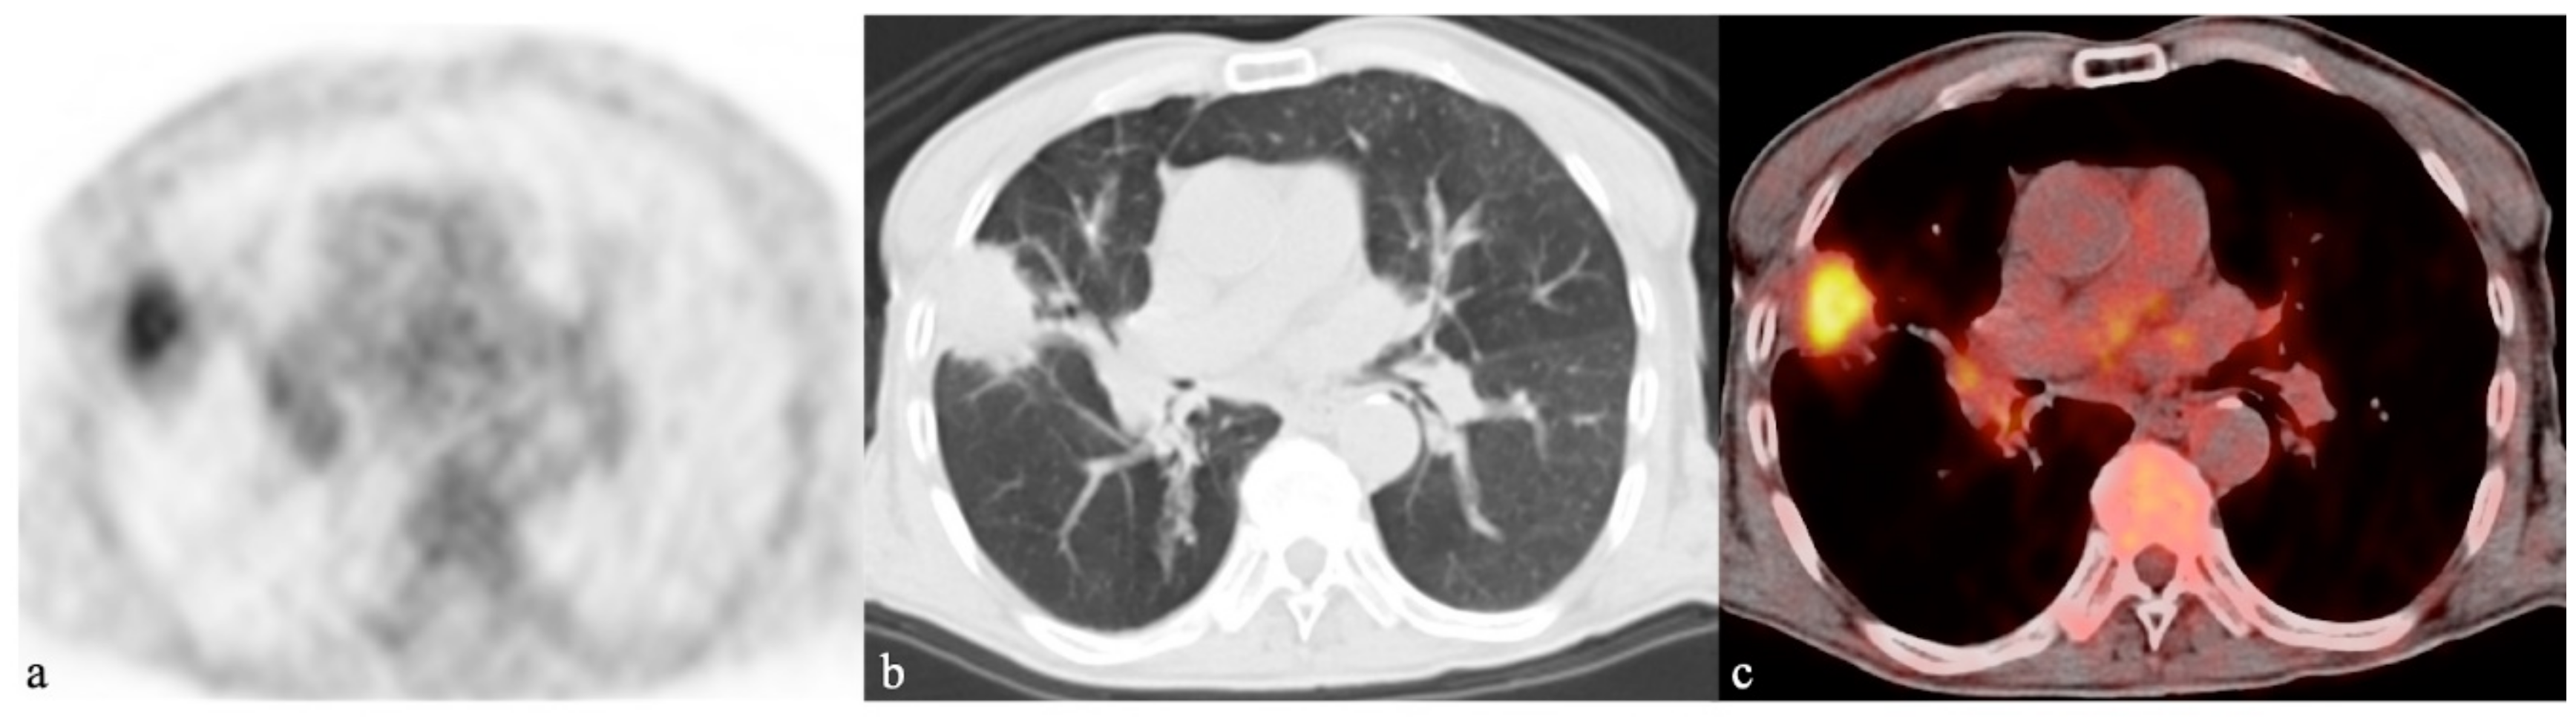

- Thomas, B.A.; Molton, J.S.; Leek, F.; Pang, Y.; Totman, J.J.; Paton, N.I.; Townsend, D.W. A comparison of 18F-FDG PET/MR with PET/CT in pulmonary tuberculosis. Nucl. Med. Commun. 2017, 38, 971–978. [Google Scholar] [CrossRef] [PubMed]